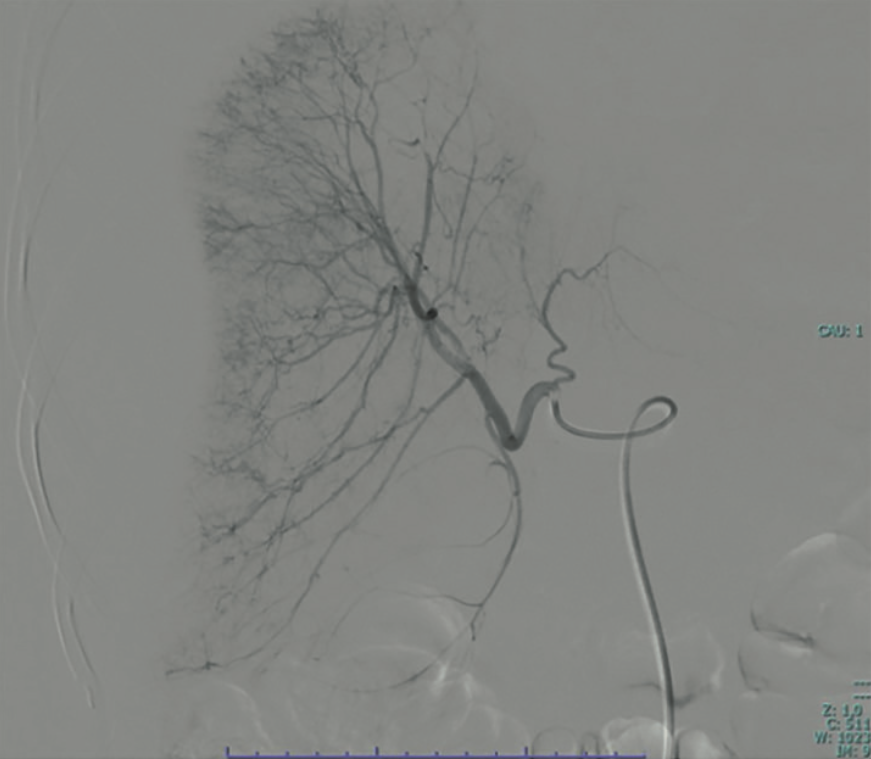

El ultrasonido y la tomografía axial computada confirmaron el hematoma subcapsular hepático que afectaba el 50% de la superficie glandular (Figura 1). La resonancia magnética sugirió un edema cerebral compatible con síndrome de encefalopatía posterior reversible (PRES). Ante el diagnóstico de hematoma hepático subcapsular y el alto riesgo de avance, se procedió a la laparotomía exploradora. Se encontró un hemoperitoneo de 200 mL y un hematoma subcapsular del 50%. Se decidió el empaquetamiento hepático y la colocación de drenajes. De manera complementaria, el radiólogo intervencionista llevó a cabo una embolización selectiva de la arteria hepática común mediante la aplicación de 5 mL de espuma hemostática, vía cateterismo del tronco celiaco (Figura 2). Luego del procedimiento, la paciente evolucionó hacia la estabilidad hemodinámica, con logro de una extubación satisfactoria y alta al servicio de ginecología al día siguiente de la embolización. Al sexto día de estancia hospitalaria la paciente se reportó consciente, orientada y con mejoría sustancial del perfil hepático (AST 420 U/L, ALT 1139 U/L) y recuperación de la función renal.

<strong>Figura 1</strong>

Figura 1. Tomografía computada de abdomen en fase simple. Se observa una colección hipodensa, de morfología biconvexa, localizada bajo la cápsula de Glisson en el lóbulo hepático derecho, compatible con un hematoma subcapsular contenido. La lesión comprime el parénquima hepático adyacente sin evidencia de extravasación franca del medio de contraste hacia la cavidad abdominal en este corte, lo que confirma la integridad capsular al momento del estudio.